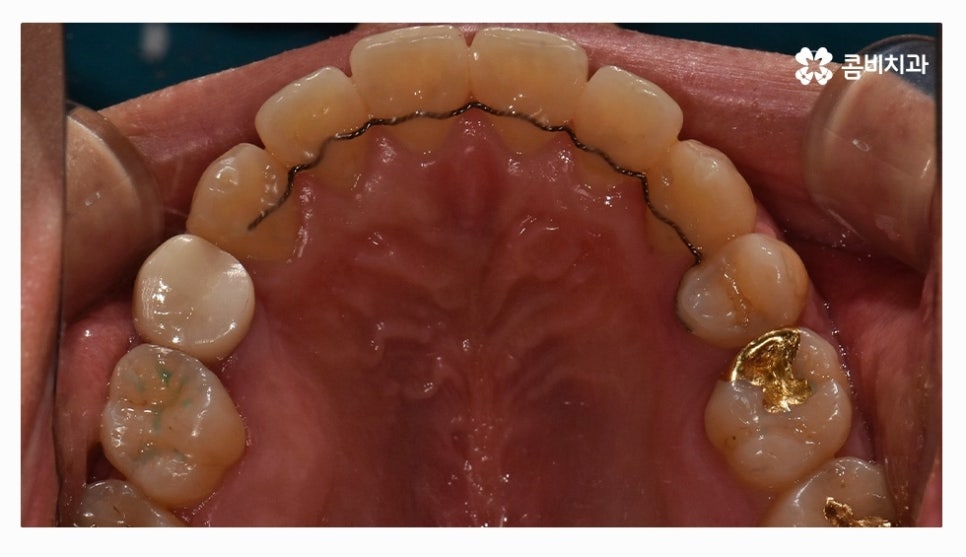

전체교정을 하시는 분들의 경우 보편적으로 많이 선택하시는

교정 장치는 클리피씨교정이라고 할 수 있을 정도로 선호도가 높으며

클리피씨교정은 자가 결찰 장치로 통증 감소 및 교정 기간을

단축시킬 수 있으며 관리가 편리하다는 장점도 갖고 있어요

클리피씨교정은 세라믹 재질이기 때문에 심미적으로도 우수한 편이며

브라켓과 와이어 고정을 위한 철사를 사용하지 않기 때문에 철사로 인해 찔리거나

입안이 뜯겨 피가 나는 경우를 예방할 수 있는데요.

클리피씨교정은 철사를 쓰지 않고 특수 클립이 내장되어

클립을 이용하여 와이어를 고정하고 열고 닫을 수 있기 때문에

교정 장치로 인한 불편함이 줄어들 수 있으며 철사를 사용하지

않는 것만으로도 보다 편안함을 느낄 수 있지만 치아를 적은 힘으로

지속적으로 이동시켜서 상대적으로 통증이 적고 치과 내원 횟수도 줄일 수 있어요.